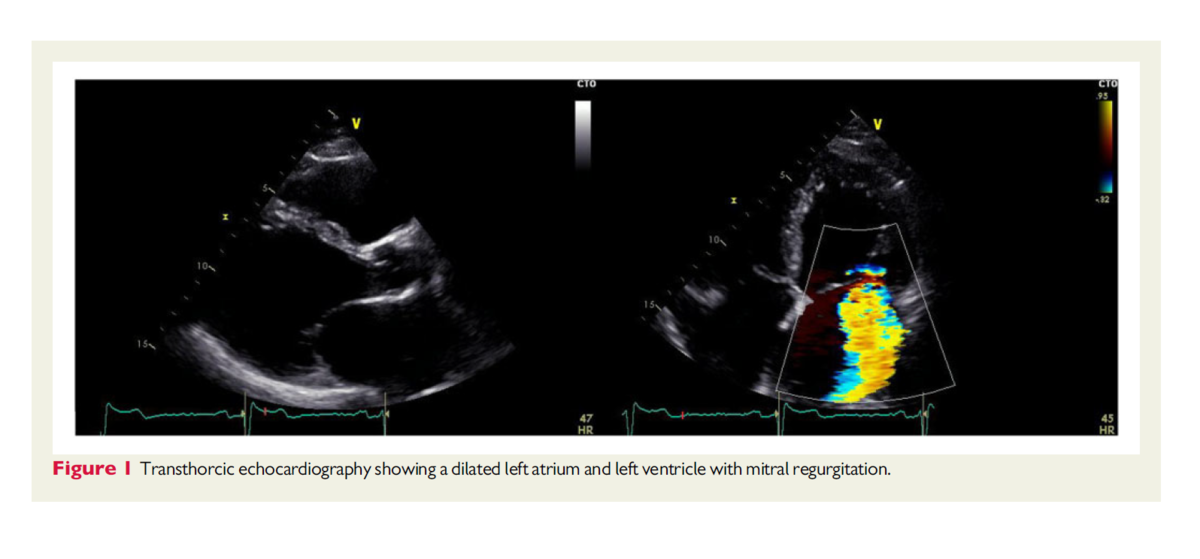

経胸壁心エコーにおいて、左心室拡大、diffuse hypokinesisに関連する収縮不全により左室駆出率は30%であった。拡大した左心房は心係数53ml/m2,縦径80mm,横径43mであり、中等度から重度の僧帽弁逆流を認めた。(図1)